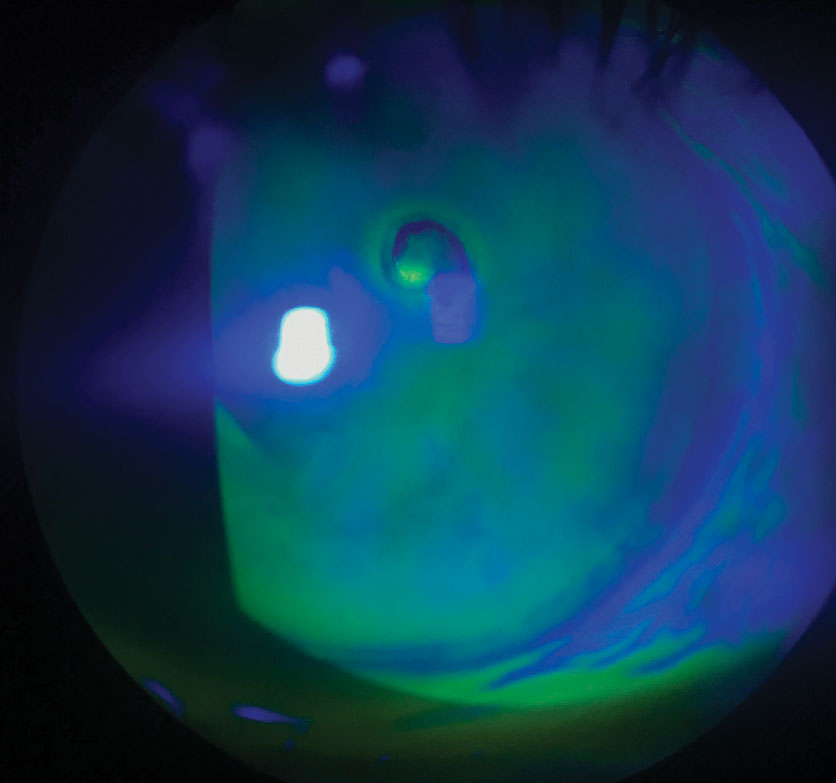

Using a slit lamp microscope, the eye care practitioner examines the corneal layers under high magnification. Eye drops containing green dye called fluorescein are usually instilled to stain the areas of missing epithelium, allowing the eye care practitioner to evaluate the size and depth of the erosion.